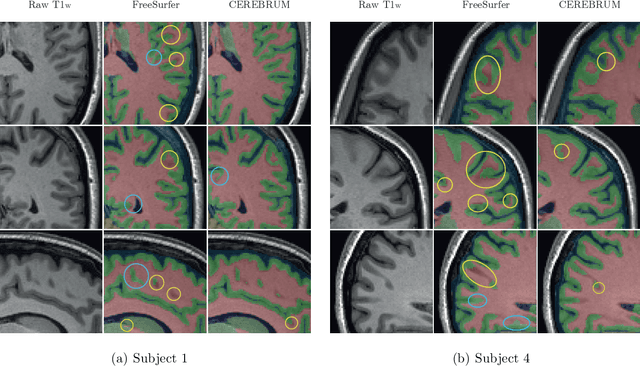

Abstract:Many functional and structural neuroimaging studies call for accurate morphometric segmentation of different brain structures starting from image intensity values of MRI scans. Current automatic (multi-) atlas-based segmentation strategies often lack accuracy on difficult-to-segment brain structures and, since these methods rely on atlas-to-scan alignment, they may take long processing times. Recently, methods deploying solutions based on Convolutional Neural Networks (CNNs) are making the direct analysis of out-of-the-scanner data feasible. However, current CNN-based solutions partition the test volume into 2D or 3D patches, which are processed independently. This entails a loss of global contextual information thereby negatively impacting the segmentation accuracy. In this work, we design and test an optimised end-to-end CNN architecture that makes the exploitation of global spatial information computationally tractable, allowing to process a whole MRI volume at once. We adopt a weakly supervised learning strategy by exploiting a large dataset composed by 947 out-of-the-scanner (3 Tesla T1-weighted 1mm isotropic MP-RAGE 3D sequences) MR Images. The resulting model is able to produce accurate multi-structure segmentation results in only few seconds. Different quantitative measures demonstrate an improved accuracy of our solution when compared to state-of-the-art techniques. Moreover, through a randomised survey involving expert neuroscientists, we show that subjective judgements clearly prefer our solution with respect to the widely adopted atlas-based FreeSurfer software.